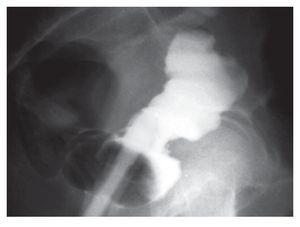

Paciente masculino de 43 años de edad, quien acude a urgencias del Hospital Escandón de Tacubaya, México, D.F., abril del 2003 por datos de estreñimiento crónico, dolor anorrectal intenso, tenesmo, sangrado transrectal escaso e imposibilidad para la defecación. Al examen físico mostraba fascie dolorosa, dolor abdominal sin datos de irritación peritoneal, abdomen distendido y al tacto rectal masa grande, la radiografía simple de abdomen mostró datos de impactación fecal importante, se realiza la desimpactación mecánica bajo sedación, luego mediante rectosigmoidoscopia (RSC) rígida se logra detectar doble lumen rectal (anterior y posterior) por encima del anillo anorrectal con úlcera fibrosa de aspecto nacarado fibrinoide de aproximadamente 3 cm de longitud por 1 cm de ancho, sobre la base del septum que separa ambos lúmenes (Imagen 1), sitio de donde se toman biopsias, posteriormente se realiza colon por enema con material hidrosoluble (Imagen 2) y se realiza colonoscopia sin encontrar patología asociada, se toman biopsias en mucosa del fondo del saco atrófico, no detectando ectopia gástrica ni displasia. Se plantea al paciente tratamiento quirúrgico; resección de saco con anastomosis coloanal a efecto de evitar nueva obstrucción intestinal a futuro, pero cuando se le informa al paciente la pequeña posibilidad del riesgo de lesión de fibras nerviosas entre las posibles complicaciones posoperatorias, se rehúsa completamente a cualquier opción quirúrgica y dado que con dieta rica en fibra notó mejoría sintomática importante sin obstrucción hasta la fecha (contacto telefónico, ya que el paciente por su propia voluntad interrumpió el seguimiento hospitalario).

Imagen 2. Colon por enema. Se aprecia llenado de la duplicación rectal pared anterior del tipo "sacular".